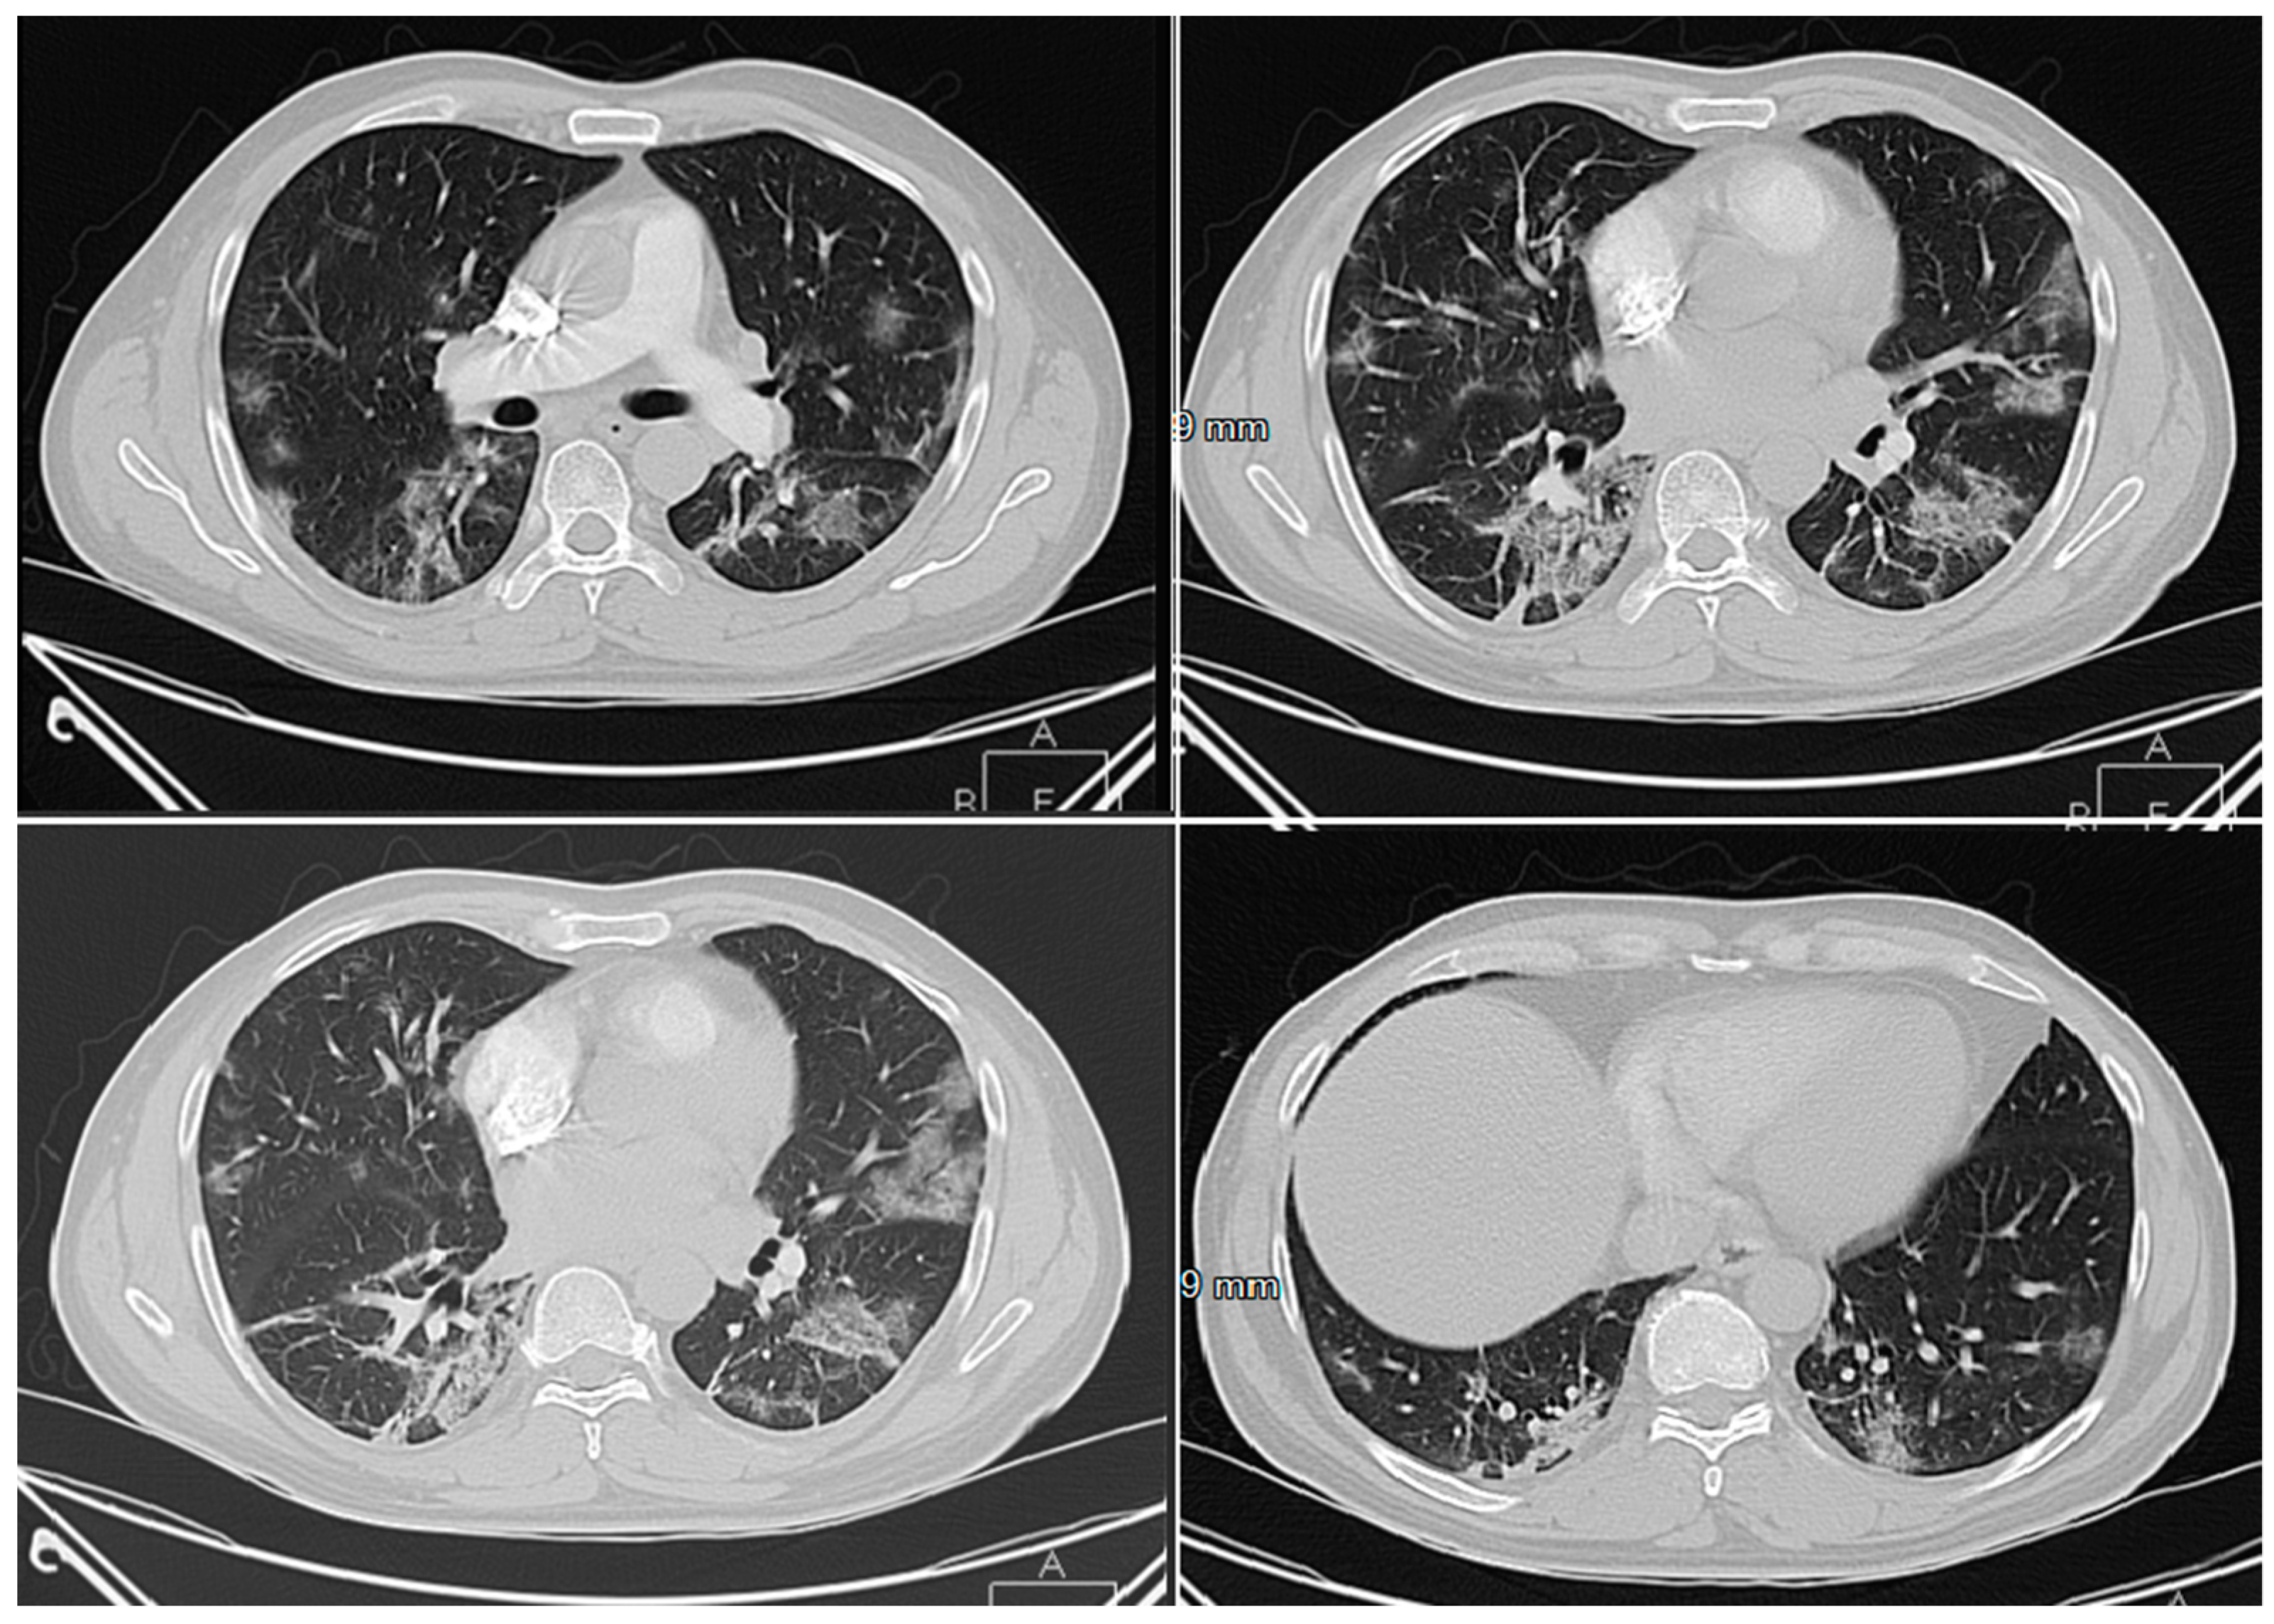

3.1.1. Cases Reports from Iran

Case 1

Case 2

Case 3

Case 4

Case 5

- Mahdavi, A.; Khalili, N.; Davarpanah, A.H.; Faghihi, T.; Mahdavi, A.; Haseli, S.; Sabri, A.; Kahkouee, S.; Kazemi, M.A.; Mehrian, P.; et al. Radiologic Management of COVID-19: Preliminary Experience of the Iranian Society of Radiology COVID-19 Consultant Group (ISRCC). Iran. J. Radiol. 2020. [Google Scholar] [CrossRef]

- Pan, Y.; Guan, H. Imaging changes in patients with 2019-nCov. Eur. Radiol. 2020. [Google Scholar] [CrossRef]

- Ng, M.-Y.; Lee, E.Y.P.; Yang, J.; Yang, F.; Li, X.; Wang, H.; Lui, M.M.-S.; Lo, C.S.-Y.; Leung, B.; Khong, P.-L.; et al. Imaging Profile of the COVID-19 Infection: Radiologic Findings and Literature Review. Radiol. Cardiothorac. Imaging 2020. [Google Scholar] [CrossRef]

- Zu, Z.Y.; Jiang, M.D.; Xu, P.P.; Chen, W.; Ni, Q.Q.; Lu, G.M.; Zhang, L.J. Coronavirus Disease 2019 (COVID-19): A Perspective from China. Radiology 2020. [Google Scholar] [CrossRef]